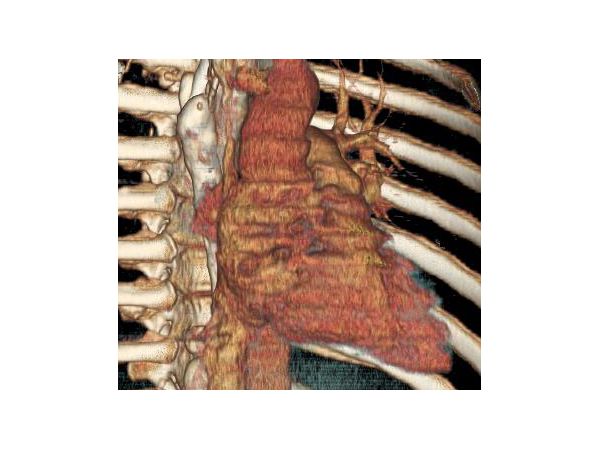

КТ грудной клетки показала:

- смещение средостение вправо;

- уменьшение объёма правого лёгкого;

- единичные плотные очаги;

- утолщение плевральных листков справа;

- сужение и изменение формы бронхов правого лёгкого, утолщение их стенок;

- небольшие отложения кальция (кальцинаты) в просвете правой лёгочной артерии;

- образование неправильной формы размером 53×36 мм без чётких контуров в проекции артерии;

- распространение образования на правый бронх, корень правого лёгкого и до 55 мм вверх по ходу верхней полой вены;

- резкое нитевидное сужение просвета верхней полой вены, видны кальцинаты;

- множество расширенных извитых вен в средостении и области грудной стенки.